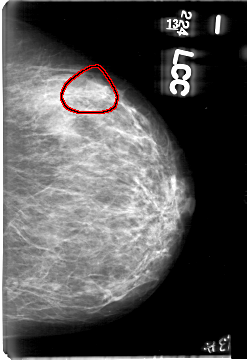

D_4061_1.LEFT_CC

LEFT_CC LINES 5386 PIXELS_PER_LINE 3691 BITS_PER_PIXEL 12 RESOLUTION 43.5 OVERLAY

FILE: D_4061_1.LEFT_CC.OVERLAY

TOTAL_ABNORMALITIES 1

ABNORMALITY 1

LESION_TYPE MASS SHAPE ROUND MARGINS OBSCURED

ASSESSMENT 0

SUBTLETY 4

PATHOLOGY BENIGN

TOTAL_OUTLINES 1

BOUNDARY